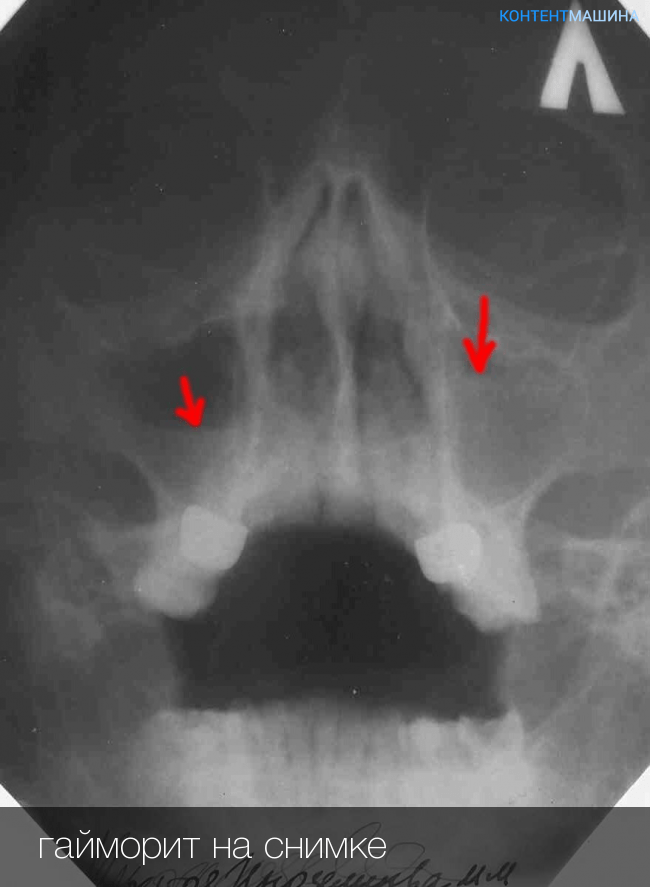

КТ-снимки хронического этмоидита: подробная визуализация